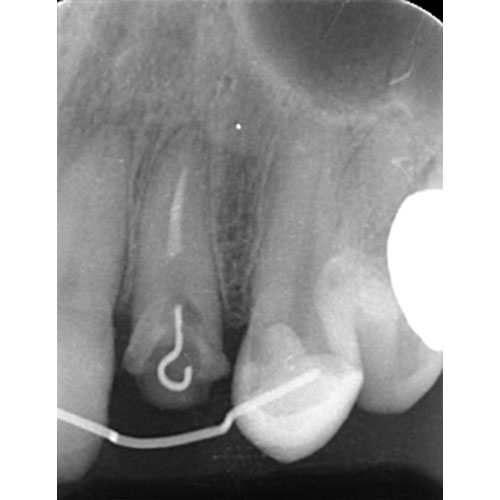

MTM開始直後と、終了後です。フックの位置が変わっているのがわかると思いますが、それが歯が動いた証拠となります。

歯からはフック、隣り合った歯にはワイヤーが渡してあります。そこにゴムをひっかけて歯を挺出させます。

| 治療前で歯根が長いのがわかります。歯根がある程度長く無いと、MTMは行えません。 | MTM終了時のもの。フックが上の金属に接している。また根尖に透過像があるが、歯が動いた証拠です。 |